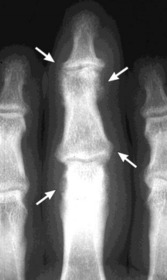

What disease is this? What do the arrows indicate? | Gout Arrows = 'punched out' erosions |

What disease is this? What indicates this? | Tophaceous gout. Soft tissue swelling surrounding the index finger PIPJ, with associated erosion and bone resorption |

What disease is this? | Tophaceous gout. |